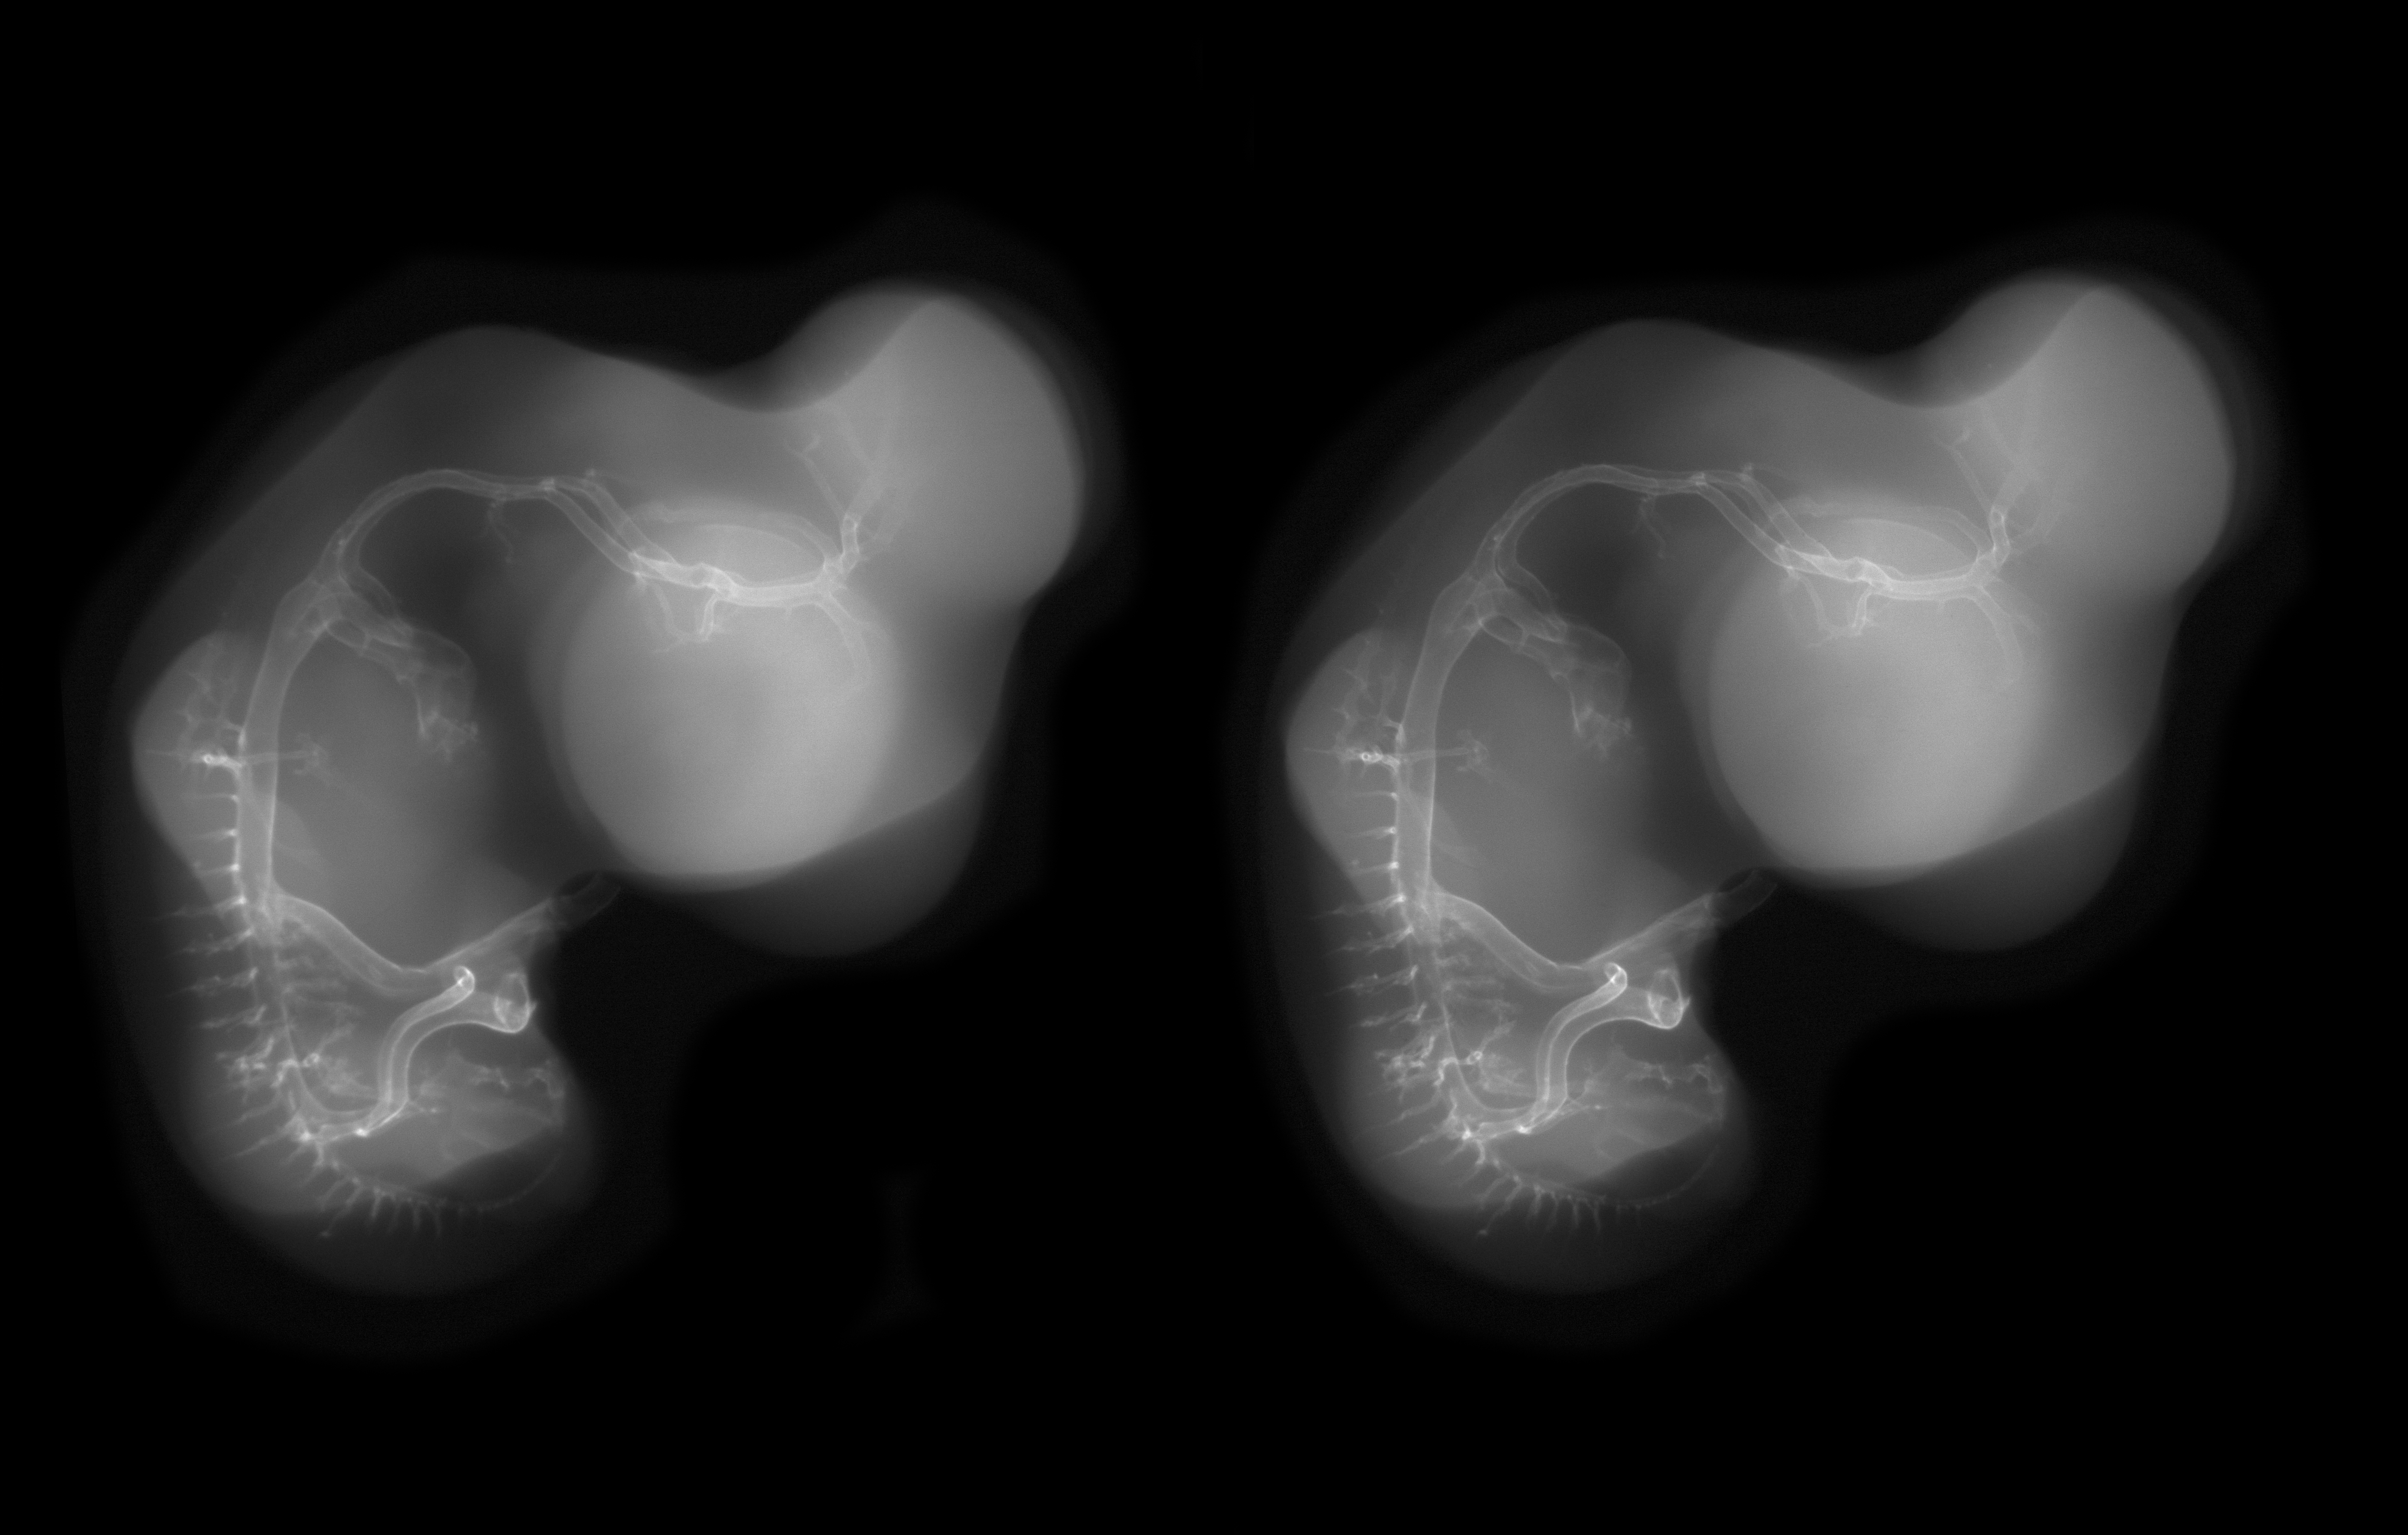

Chick Embryo Microangiography

Hamburger-Hamilton (HH) Stage 28 (approx. 5.5 - 6 days)

Stereo X-Ray Micrographs